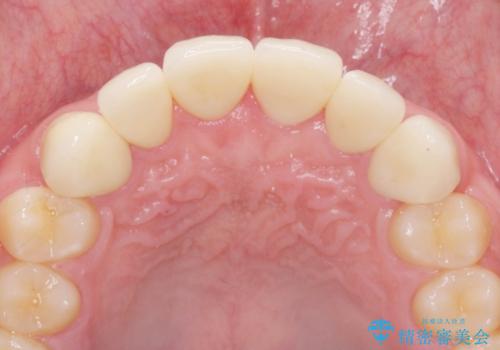

歯周外科を行ったことで、歯ぐきの形態や腫れが改善され、審美性だけでなく清掃性も大きく改善することができました。